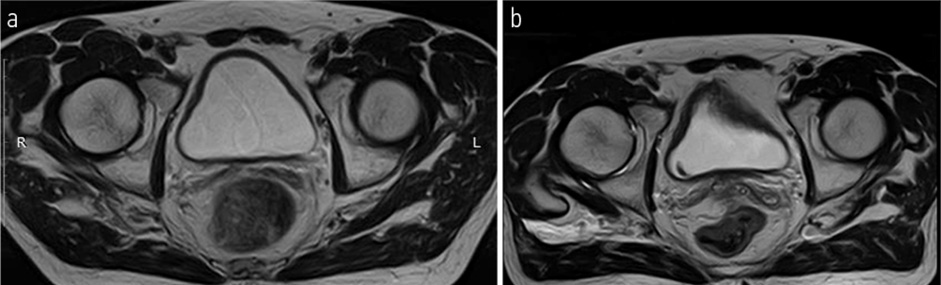

МРТ органов большого таза – ОБП (14.10.2021): По заднеправой стенке мочевого пузыря, в том числе на уровне устья правого мочеточника, визуализируется опухолевое образование неправильной формы с нечеткими неровными контурами со смешанным характером роста. Размер эндофитного компонента 40×21 мм, размер экзофитного компонента – 8×6 мм. Образование вовлекает всю толщу стенки с распространением процесса в паравезикальную клетчатку. Получена МР-картина Cr. мочевого пузыря с выходом процесса за пределы стенки. Удвоение правого мочеточника, уретероэктазия справа. Гиперплазия предстательной железы с наличием участка измененного МР-сигнала в транзиторной зоне левой доли (PI-RADS-4). Метастазы в кости таза. В сравнении с данными исследованиями от 27.08.2021 отмечается отрицательная динамика (рис. 2).

Рис. 2. МРТ ОМТ от 14.10.2021: опухолевое образование неправильной формы с нечеткими неровными контурами со смешанным характером роста. Размер эндофитного компонента – 40×21 мм, размер экзофитного компонента – 8×6 мм.

Fig. 2. Pelvic magnetic resonance imaging (MRI) dated 14.10.2021: tumor mass of irregular shape with ill-defined uneven contours with a mixed growth pattern. The size of the endophytic component is 40×21 mm, and the size of the exophytic component is 8×6 mm.

Рис. 4. МРТ ОМТ от 14.10.2021 в сравнении с МРТ от 27.12.2021. Состояние после 3-го курса лекарственного лечения по схеме EP: опухолевое образование неправильной формы с нечеткими неровными контурами со смешанным характером роста размерами до 14×11 мм с внутрипросветным компонентом.

Fig. 4. Pelvic MRI dated 14.10.2021 in comparison with MRI dated 27.12.2021. State after the 3rd course of drug treatment according to the EP regimen: tumor mass of irregular shape with ill-defined uneven contours with a mixed growth pattern up to 14×11 mm with an intraluminal component.

Пациенту Н. с 11.2021 по 03.2021 проведено 6 курсов АПХТ по схемe EP. По результатам контрольного обследования отмечена выраженная положительная динамика в виде отсутствия опухолевого роста перивезикально и в полости мочевого пузыря (МРТ ОМТ от 24.03.2022); рис. 4, 5. Очаговые изменения костей скелета без динамики (сцинтиграфия скелета от 25.03.2022). Онкомаркеры (27.12.2021): винилминдалевая кислота – 5,3; гомованилиновая кислота – 5,8; 5-оксииндолуксусная кислота – 4,5, хромогранин А – 0,96; нейронспецифическая енолаза – 13,48; серотонин – 29,7. Учитывая выраженный положительный эффект на фоне ранее проводимого лечения, морфологическую структуру опухоли, рекомендована монохимиотерапия (МХТ) препаратом этопозид (100 мг 1–10-й дни, курс 21 день) до прогрессирования или неприемлемой токсичности с контрольным обследованием через 3 курса.